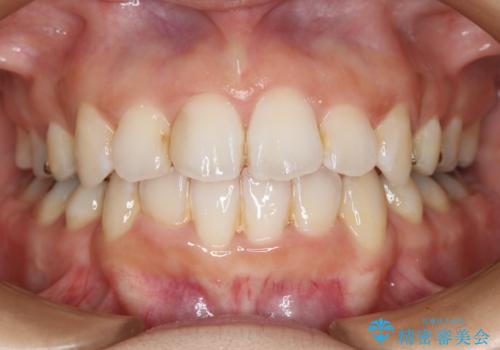

- 歯のガタつきと出っ歯が気になるので矯正治療を希望し来院された患者様です。

上下顎とも歯を並べられるスペースが無く、口元を下げたいというご希望だったので、抜歯とワイヤー矯正を併用した治療を計画しました。

抜歯スペースを利用し口元を大きく下げることが出来ました。